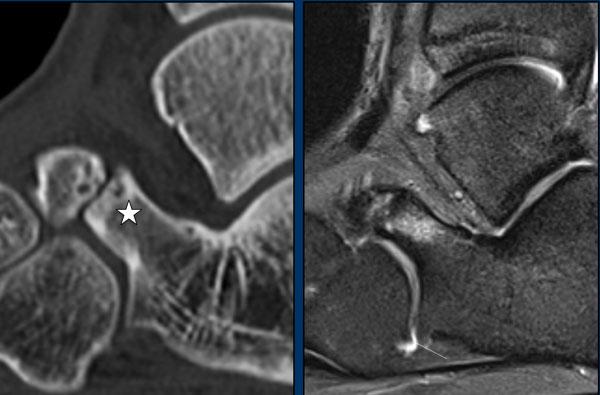

case 5 – chronic pain

The findings are:

- narrowing of the posterior subtalar joint with sclerosis

- C sign

Khớp dưới sên bao gồm các diện khớp trước, giữa và sau. Hợp khối xương sên-gót thường gặp nhất ở diện khớp giữa tại mức độ của mỏm chống sên.

Hợp khối xương sên-gót có thể khó quan sát trên các tư thế chụp X-quang tiêu chuẩn của bàn chân do hướng phức tạp của khớp dưới sên.

Một số dấu hiệu X-quang thứ phát của liên hợp xương sên-gót đã được mô tả, bao gồm:

- Talar beak

- Narrowing of the posterior subtalar joint

- Rounding of the lateral talar process

- Thiếu hình ảnh mô tả các diện khớp giữa trên phim X-quang thẳng.

- C-sign

Mỏ xương sên xảy ra do sự suy giảm chuyển động của khớp dưới sên, dẫn đến xương thuyền trượt lên trên xương sên. Sự nâng màng xương xảy ra tại điểm bám của dây chằng sên-thuyền, và cuối cùng, một chu kỳ sửa chữa xương dẫn đến sự hình thành mỏ xương sên.

Dấu hiệu “C” là một đường hình chữ C trên phim chụp nghiêng, phác thảo vòm xương sên phía trong và xương chêm sau dưới. Dấu hiệu C xuất hiện do sự cầu nối xương giữa vòm xương sên và xương chêm, cũng như đường viền dưới nổi bật của xương chêm.

Khi chùm tia X chiếu tiếp tuyến với đường viền sau dưới của xương chêm bất thường trên một khoảng cách dài, một hình chữ “C” liên tục được tạo thành. Dấu hiệu C có thể được quan sát thấy trong cả các liên kết xương và không xương.

Hình ảnh

Trên hình ảnh T1W, có sự hợp nhất xương và cứng khớp của xương sên với xương gót.